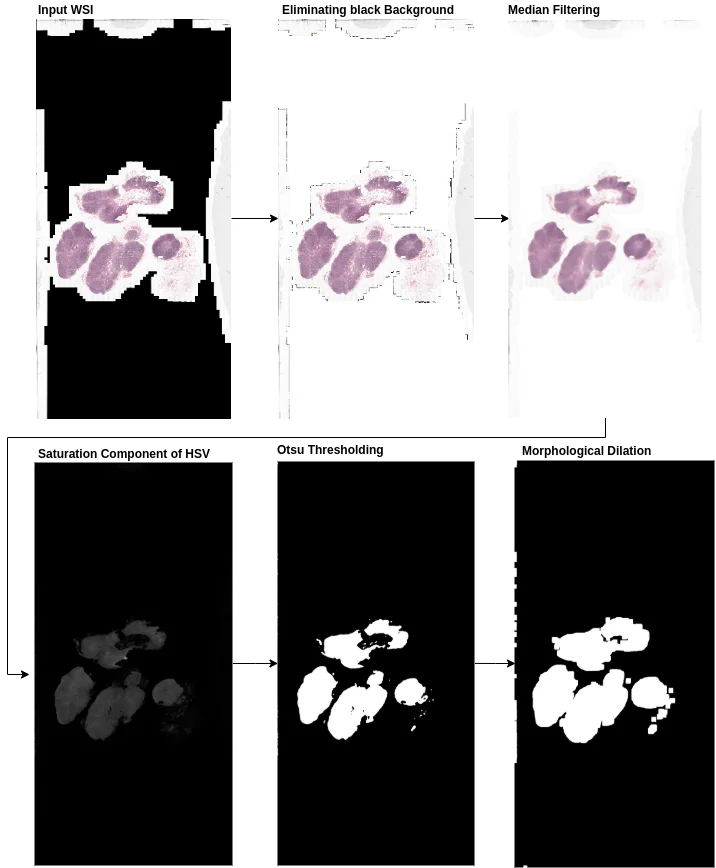

The training pipeline divides WSIs into smaller image patches for efficient training, while the inference pipeline introduces a patch coordinate sampling grid from post-processed tissue masks to reduce computational time by discarding non-tissue patches. The authors also address edge artifacts in patch-based segmentation through averaging prediction probabilities at overlapping regions and using large patch sizes during inference.